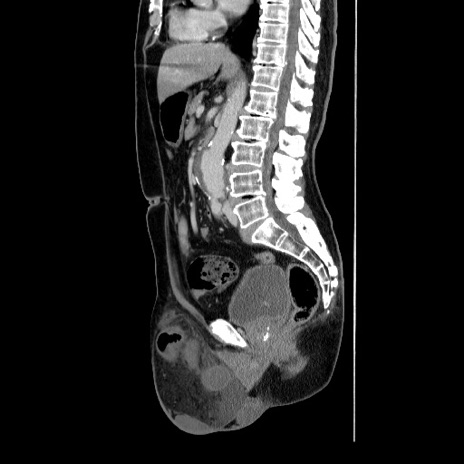

症例34(矢状断像)

【症例】60歳代 男性

【主訴】右鼠径部膨隆

【現病歴】1年程前より右鼠径部膨隆あり。自己にて還納可能だったため放置していた。3時間前より右鼠径部の脱出を認め、還納困難となり受診。

【身体所見】右鼠径部に小児頭大の膨隆あり。弾性硬であり、用手還納は困難。左鼠径部にも膨隆を認める。脱出はなし。